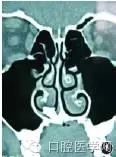

鼻竇CT(圖1)回報:高密度影像,懷疑鼻腔異位牙。

圖1 竇CT可見額外牙位于右側(cè)鼻腔

額外牙多為孤立牙,且牙根相對較短小。鼻腔牙多發(fā)于鼻底,以上頜切牙或尖牙最常見,本例為多生牙。口腔曲面斷層片可見鼻底牙齒狀高密度陰影,鼻竇CT片鼻底見橫置或豎置牙樣的高密度影,有時其中還可見牙髓腔低密度影,往往牙根在鼻腔底部骨質(zhì)內(nèi),而牙冠向鼻腔內(nèi)突出。觀察鼻竇CT片時應注意異位牙與上頜骨的關(guān)系,牙根位于骨內(nèi)多少,以評估手術(shù)難度。